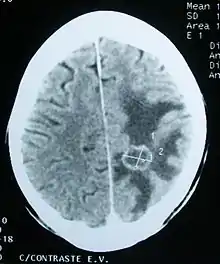

Imaging

Medical imaging plays a central role in the diagnosis of brain tumors. Early imaging methods – invasive and sometimes dangerous – such as pneumoencephalography and cerebral angiography have been abandoned in favor of non-invasive, high-resolution techniques, especially magnetic resonance imaging (MRI) and computed tomography (CT) scans,[37] though MRI is typically the reference standard used.[39] Neoplasms will often show as differently colored masses (also referred to as processes) in CT or MRI results.

- Benign brain tumors often show up as hypodense (darker than brain tissue) mass lesions on CT scans. On MRI, they appear either hypodense or isointense (same intensity as brain tissue) on T1-weighted scans, or hyperintense (brighter than brain tissue) on T2-weighted MRI, although the appearance is variable.

- Contrast agent uptake, sometimes in characteristic patterns, can be demonstrated on either CT or MRI scans in most malignant primary and metastatic brain tumors.

- Pressure areas where the brain tissue has been compressed by a tumor also appear hyperintense on T2-weighted scans and might indicate the presence a diffuse neoplasm due to an unclear outline. Swelling around the tumor known as peritumoral edema can also show a similar result.

This is because these tumors disrupt the normal functioning of the BBB and lead to an increase in its permeability. More recently, advancements have been made to increase the utility of MRI in providing physiological data that can help to inform diagnosis and prognosis. Perfusion Weighted Imaging (PWI) and Diffusion Weighted Imaging (DWI) are two MRI techniques that reviews have been shown to be useful in classifying tumors by grade, which was not previously viable using only structural imaging.[40] However, these techniques cannot alone diagnose high- versus low-grade gliomas, and thus the definitive diagnosis of brain tumor should only be confirmed by histological examination of tumor tissue samples obtained either by means of brain biopsy or open surgery. The histological examination is essential for determining the appropriate treatment and the correct prognosis. This examination, performed by a pathologist, typically has three stages: interoperative examination of fresh tissue, preliminary microscopic examination of prepared tissues, and follow-up examination of prepared tissues after immunohistochemical staining or genetic analysis.